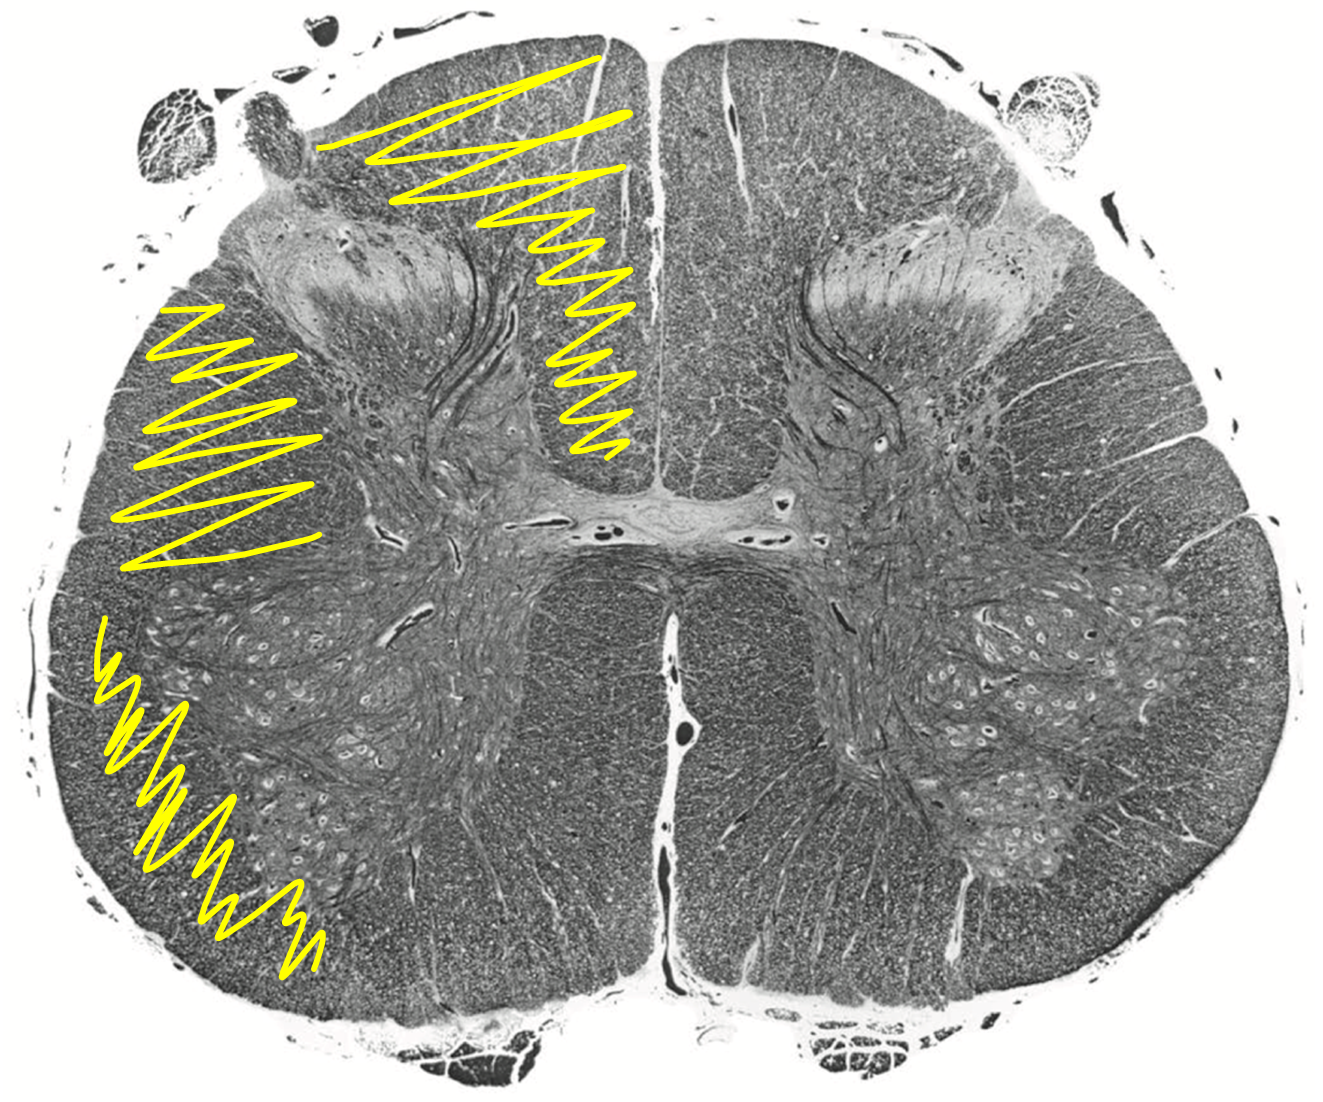

Yellow Periaqueductal gray in brainstem

Pain modulation

Pain modulating products activated by periaqueductal gray

Serotonin

Norepinephrine

Endogenous opiate peptides (e.g., enkephalins)

Periaqueductal Gray

for pain modulation